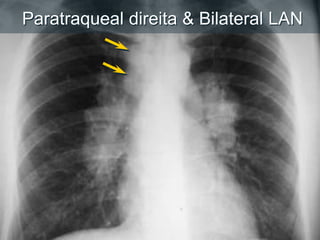

Linfoadenopatia

Paratraqueal direita & Bilateral LAN